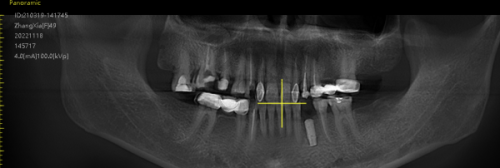

我第一次来到青岛维乐口腔医院时,就被医院的环境所吸引。医院的装修简洁大方,给人一种舒适、干净的感觉。前台的工作人员非常热情,特别快就帮我办理好了挂号手续,并引导我到候诊区等待。不一会儿,就轮到我就诊了。医生先是详细地询问了我的病史和牙齿情况,然后对我的口腔进行了全方面的检查。检查项目包括口腔X光片、口腔CT等,这些检查能够让医生更正确地了解我的牙齿状况和骨量情况。检查结束后,医生根据我的检查结果,为我制定了详细的门牙种植方案,并耐心地向我解释了整个种植过程和注意事项。我对医生的专精和耐心非常满意,当场就决定接受种植治疗。

种植手术后,就是漫长的愈合期了。在这个阶段,我需要按照医生的嘱咐,注意口腔卫生,避免食用实力强、过烫的食物,以免影响种植体的愈合。刚开始的时候,伤口还有些疼痛和肿胀,但随着时间的推移,这些症状逐渐减轻。我每天都会认真刷牙、漱口,使用医生推荐的口腔护理产品,保持口腔的清洁。在愈合期内,我还按照医生的要求定期来医院复诊,医生会通过口腔X光片等检查方式,观察种植体的愈合情况。每次复诊,医生都会详细地跟我讲解种植体的愈合情况,并给予我一些饮食和口腔护理方面的建议。在医生的悉心指导下,我的种植体愈合得非常好。